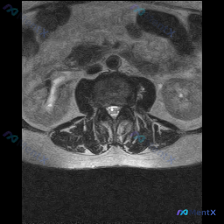

看到这个读片需求,整理了完整的分析思路分享给大家。 病例基础信息 用户提供一张腹部MRI轴位T2加权图像,问题是:判断这张影像上是否存在椎间盘病变。 第一步:影像基础评估 先给大家整理这份影像的客观发现: 1. 图像质量:对比度良好,能清晰显示腹膜后结构,无明显运动伪影 2. 解剖定位:这是上腹部/...

看到一个挺有警示意义的读片场景,整理出来和大家分享一下。 基本临床场景 临床怀疑患者存在椎间盘病变,提供了一张T2加权冠状位磁共振影像,请读片判断是否存在椎间盘病变,拿到的影像分析结果如下: 现有影像分析内容: 1. 双侧肾脏轮廓清晰,位置大小正常,肾周脂肪间隙清晰,无渗出模糊影 2. 肾脏皮髓质分...